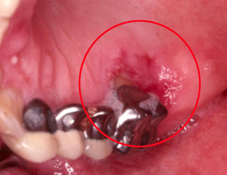

圖二及圖三、口腔或舌頭的內壁上會出現白色或紅色斑塊

■ 口腔或舌頭的內壁上會出現白色或紅色斑塊(如圖二、圖三)。